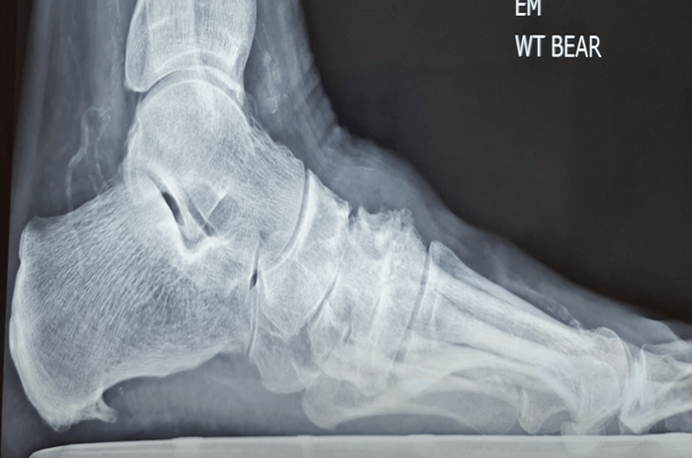

What is Dorsal Midfoot Exostosis?

A dorsal midfoot exostosis is a painful bony growth that develops on the top of the foot, specifically at the metatarso-cuneiform joint (top of the arch). This condition often presents as a noticeable bump that can cause discomfort, especially when wearing enclosed footwear.

You will generally notice the dorsal midfoot exostosis growing over time – you may notice a hard, raised bump on the top of the foot. While the bony growth itself may not always be painful it can cause pain by rubbing on shoes, formation of wounds/skin breakdown constant redness and swelling in the area.